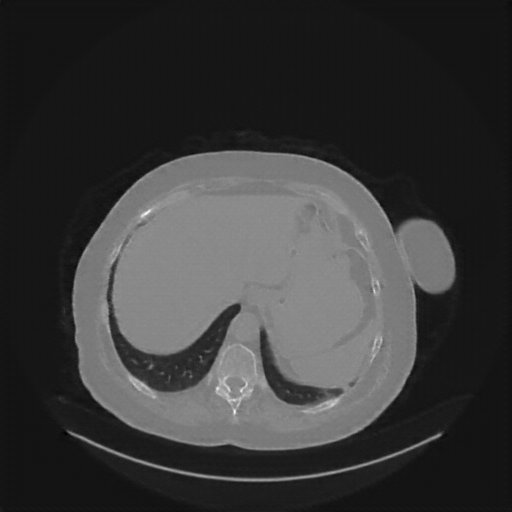

Original VENOUS CT scan

No window - Raw intensity values

Lung window (WL -600, WW 1500 β†’ Low βˆ’1350, High +150)

Mediastinum window (WL 40, WW 400 β†’ Low βˆ’160, High +240)